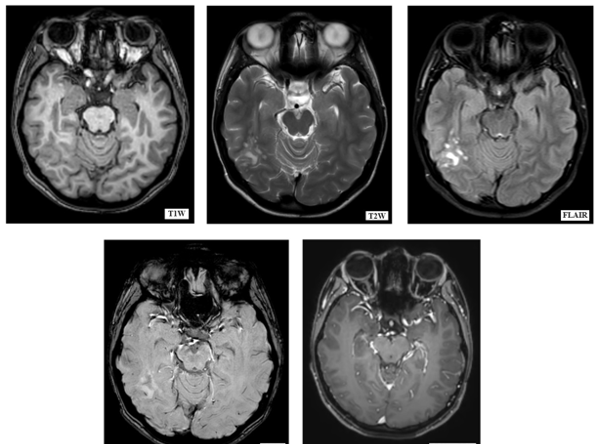

MRI brain with contrast (Figure.1)

Figure 1: MRI Brain plain and contrast of the patient that shows a cluster of coalescent nodules in the posterior aspect of right temporal and right tempero-parietal lobes.

Was done, that revealed a small cluster of well defined, high T2W/ FLAIR weighted coalescent nodules in the subcortical and periventricular white matter of the posterior aspect of right temporal and right tempero-parietal lobes. Overlying cortex is not thickened which was suggestive of multinodular vacuolating neuronal tumor.

On CT imaging, they are difficult to identify, yet as described by Nagaishi et al4., in some patients they are seen as hypo dense and non-enhancing lesion in the subcortical white matter. MRI is considered as gold standard imaging for these lesions. They are seen as a group of nodules on the inner surface of the cortex. Nodules are hyperintense to the adjacent white matter on T2W and FLAİR images. They are isointense or mildly hypointense on T1W. They typically exhibit no diffusion restriction or contrast enhancement. They demonstrate no blooming on susceptibility-weighted imaging.